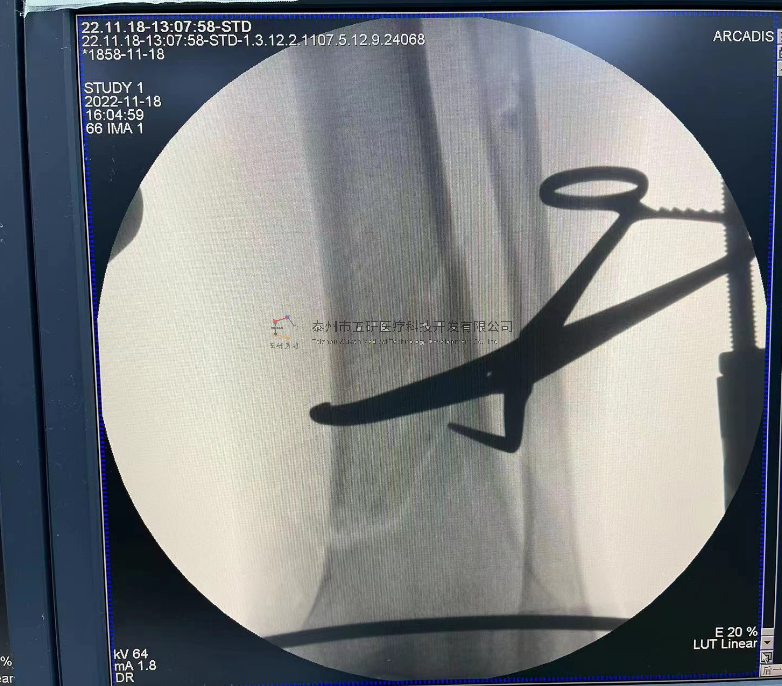

【影像圖片—術(shù)后】

【手術(shù)資料】